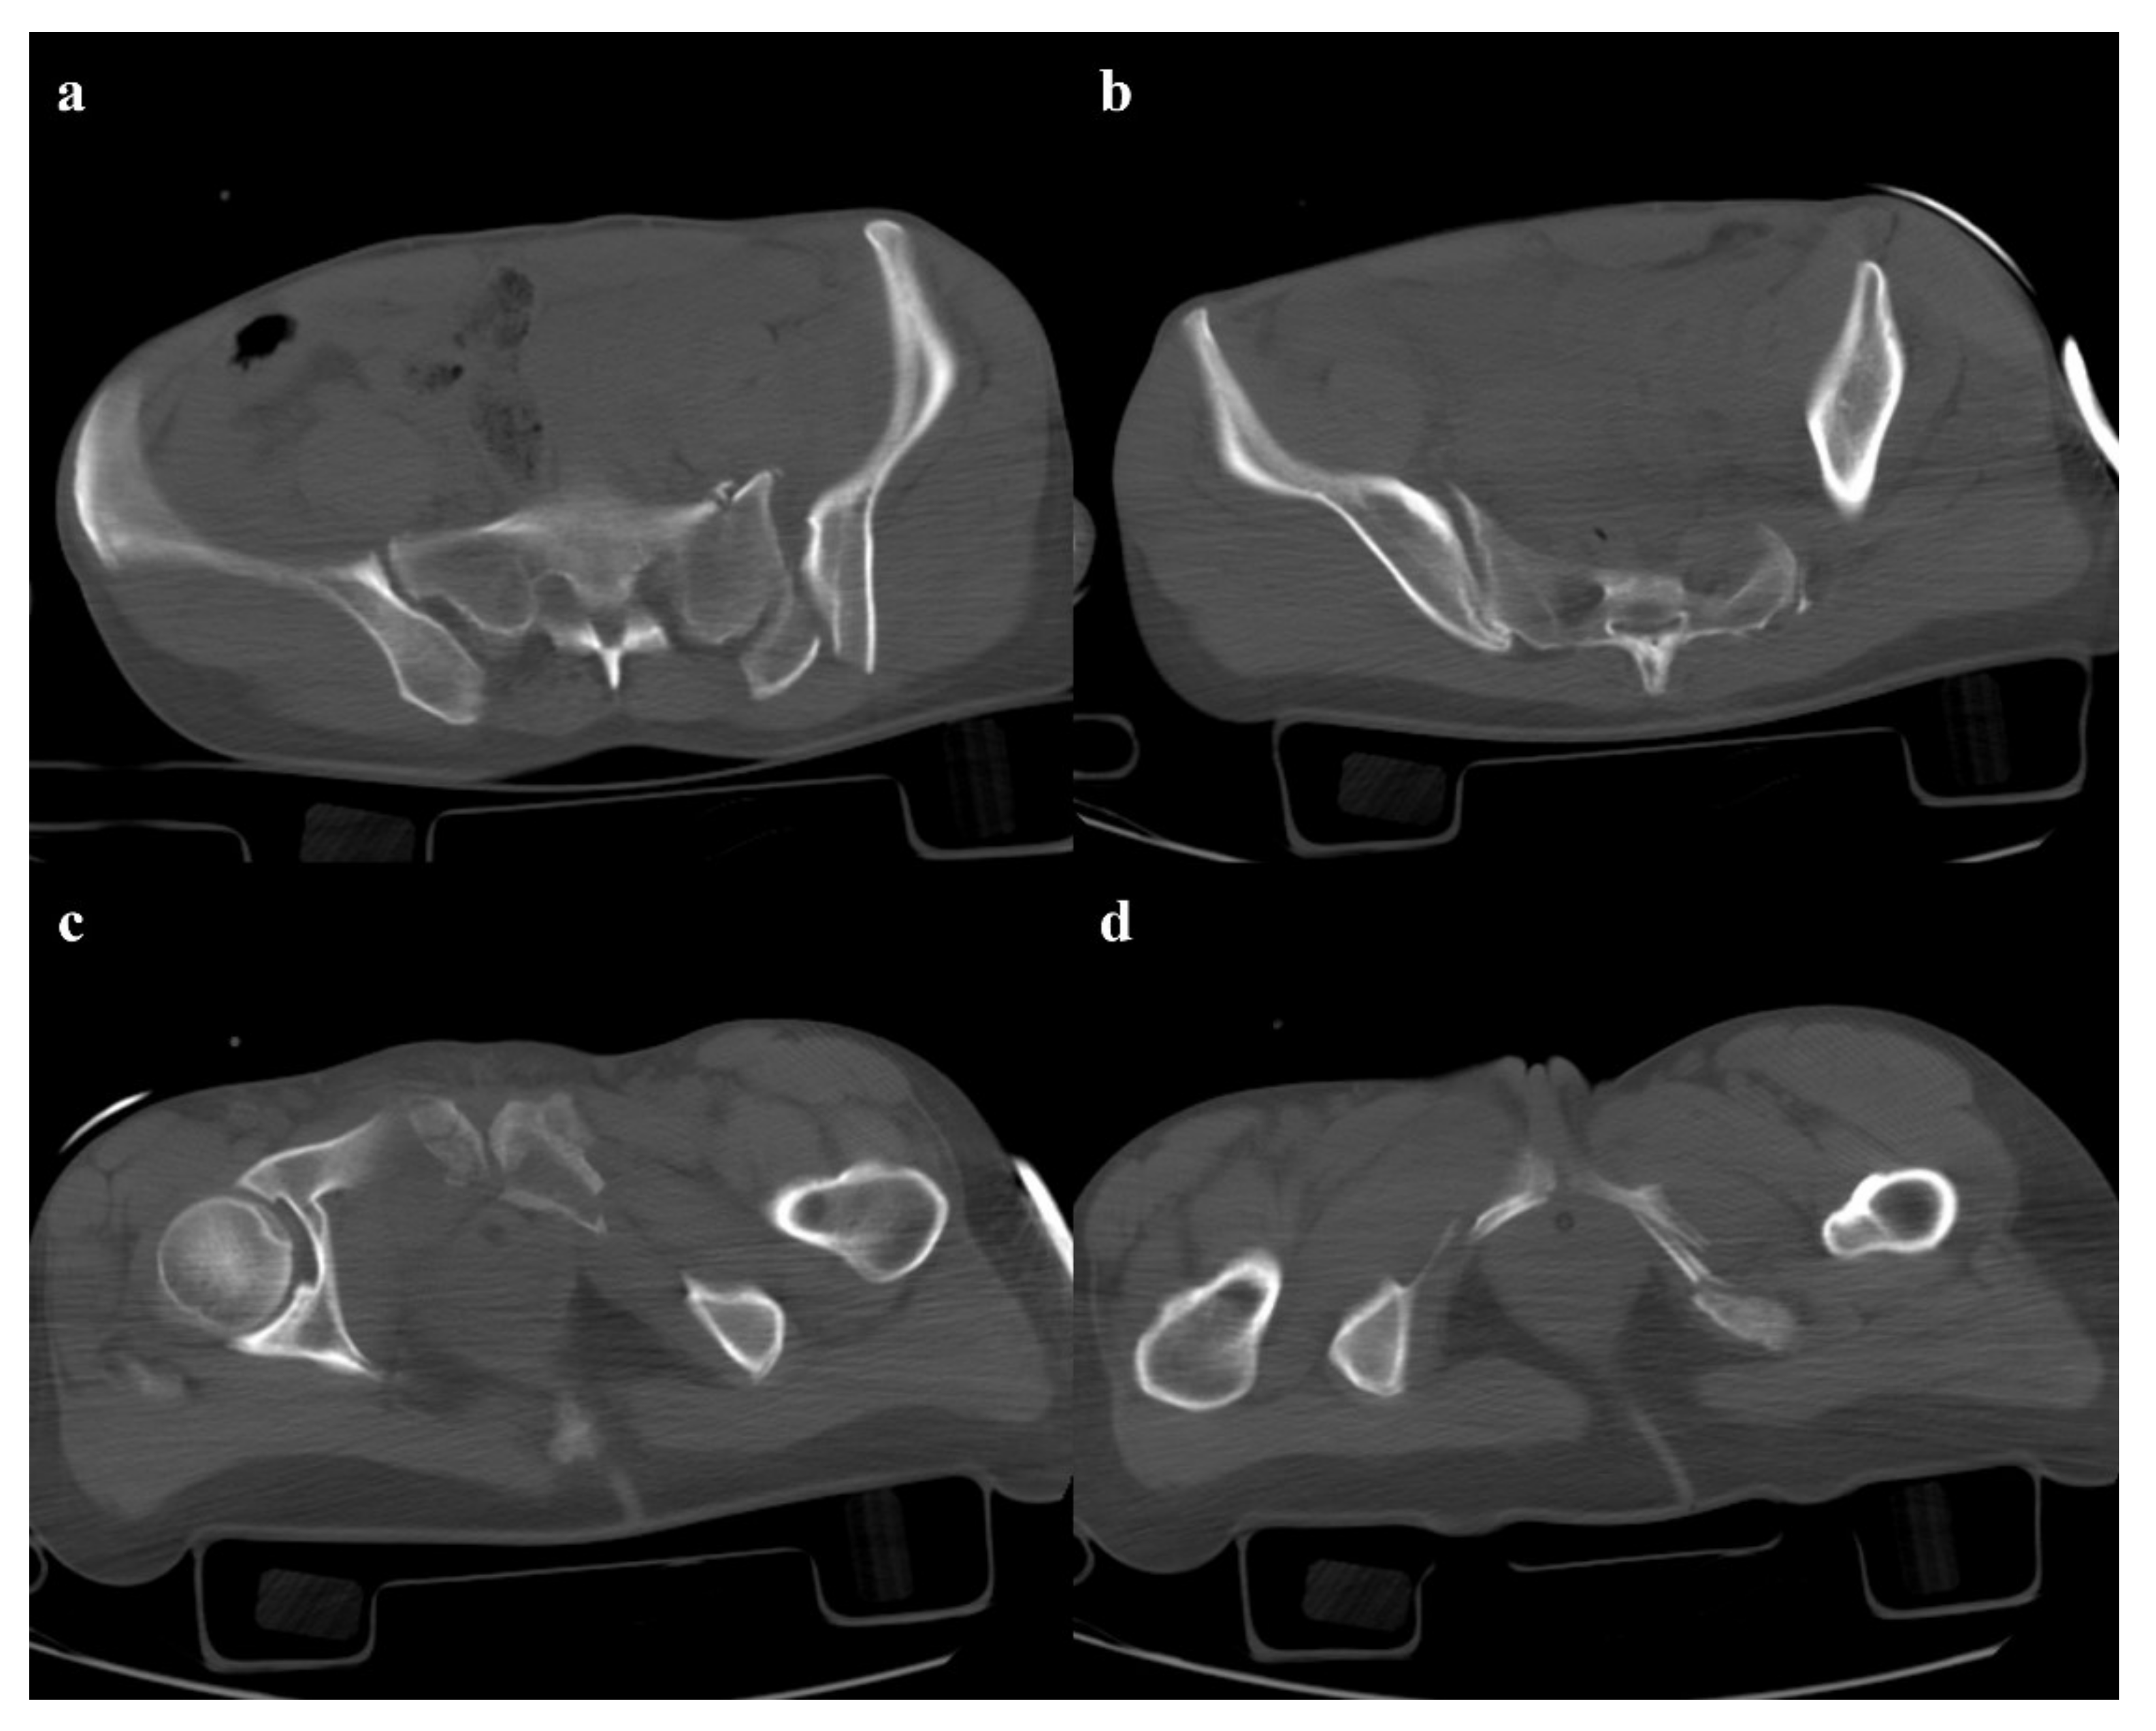

• Grade 3: the lateral compression force is associated with a contralateral anteroposterior compression force, with an external rotation of the contralateral hemipelvis (“windswept pelvis”). Grade 1 or grade 2 lateral compression injuries are associated with a contralateral sacroiliac joint diastasis (Figure 3). Lateral compression grade 3 injuries have a multidirectional instability and require a stable internal fixation [3]. In these lesions, an adjunctive temporary external fixation is useful [3].

Figure 3. Lateral compression fracture, type 3. Axial CT images show the fracture of the iliac and sacral wings on the left side (a), anterior widening of the right sacroiliac joint (b), and fracture of bilateral pubic branches (c,d).